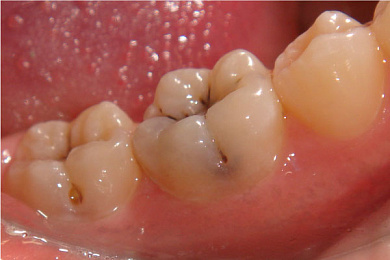

Многие родители считают, что молочные зубы можно вообще не лечить, поскольку вскоре они сменятся на постоянные. К сожалению, это огромное заблуждение. Дело в том, что игнорирование проблемы может вызвать ряд осложнений:

неправильное направление роста постоянных зубов;

повышение вероятности возникновения периодонтита и пульпита;

появление боли и отеков;

переход кариеса на постоянные зубы.